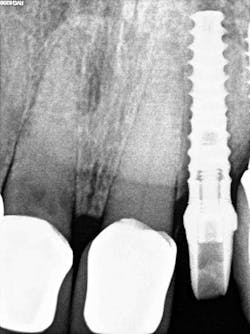

The decision to use the Ditron Implant System was based on the following treatment plan: extraction and immediate implant placement, with immediate provisionalization using a final titanium abutment. Extraction and immediate implant placement with immediate provisionalization have shown to be quite successful.

Maintaining initial stability is important when an implant is placed in a compromised extraction site, since there is less bone-to-implant contact there than in a healed site. Because of its architecture, the Ditron Ultimate implant offers a very high initial stability and strong abutment connection. The implant profile uniformly distributes the stress directly to the bone, which results in a more even distribution of force and lower long-term crestal resorption. This implant system has a good aggressive thread profile and a secure abutment connection, which are both key characteristics. The microthreads on the implant’s reverse conical neck (RCN) greatly increase the implant’s ability to resist axial displacement, and the mechanical stimulus the microthreads provide helps to preserve the peri-implant marginal bone. By inserting an Ultimate implant, 5.57 mm3 of bone will be saved compared to that of a non-RCN implant.7